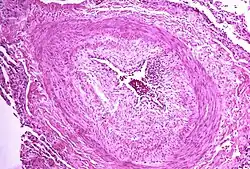

.jpg)

PAH is considered a universally fatal illness, although survival time may vary between individuals. The prognosis of pulmonary arterial hypertension (WHO Group I) has an untreated median survival of 2–3 years from time of diagnosis, with the cause of death usually being right ventricular failure (cor pulmonale).[98] The survival time is variable and depends on many factors.[99] A recent outcome study of those patients who had started treatment with bosentan (Tracleer) showed that 89% of patients were alive at 2 years.[100] With new therapies, survival rates are increasing. For 2,635 patients enrolled in The Registry to Evaluate Early and Long-term Pulmonary Arterial Hypertension Disease Management (REVEAL Registry) from March 2006 to December 2009, 1-, 3-, 5-, and 7-year survival rates were 85%, 68%, 57%, and 49%, respectively. For patients with idiopathic/familial PAH, survival rates were 91%, 74%, 65%, and 59%.[101] Levels of mortality are very high in pregnant women with severe pulmonary arterial hypertension (WHO Group I). Pregnancy is sometimes described as contraindicated in these women.[102][103][104]